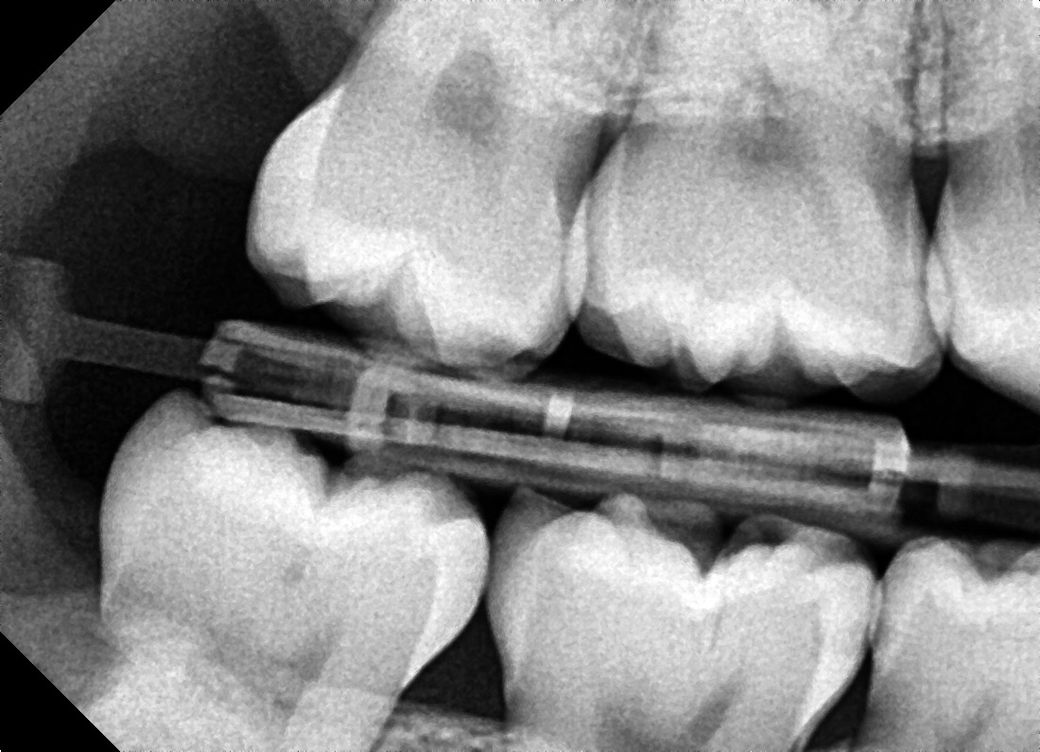

치과 의견이 너무 다릅니다.. 인접면 충치 관련 알려주세요

사진도 제일 많이 찍고 엑스레이사진이 제 주관상 가장 좀 선명?했습니다 인접면 충치가 9개 정도 모인다고 최소 198만원에서 271만원으로 인레인, 레진 치료를 해야한다고 합니다

사진은 a치과 엑스레이 사진입니다!

엑스레이 상으로는 인접면에 충치가 많이 있는걸로 보입니다. 일단 3개월정도 관리를 해보고 그때 가셔서 충치가 진행되면 치료를 진행하시고 관리가 잘되면 계속해서 관리를 해볼것같습니다.

정확한 검사는 따로 해봐야 겠으나 사진상으로는 명확히 충치가 여러군데에서 진행되고 있습니다.

방사선 사진상으로는 작은 충치가 보이긴 하지만 정확한 확인을 위해서는 육안으로 확인을 해야 합니다. 하지만 방사선 사진상으로는 그렇게 큰 충치는 보이지 않습니다.

B 치과 말이 맞습니다. 충치 조금 있는 것은 지켜 보다가 더 진행되면 해도 됩니다. 아마도 A치과는 상담원이 상담했을 가능성도 있습니다.